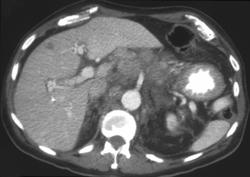

Gastric Cancer Metastatic to Bone